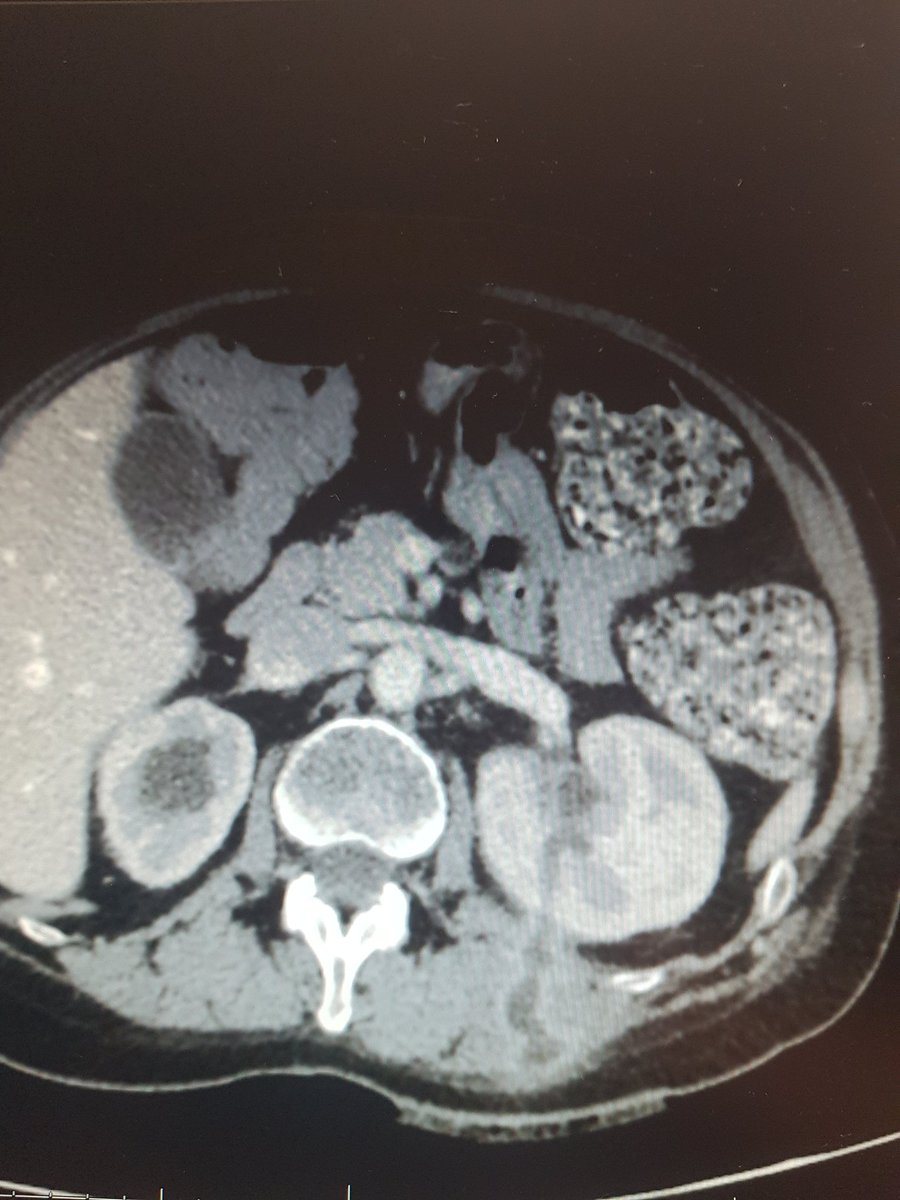

I'd perform a laparoscopyc approach, drain the urine in the surgery. This is not a inflammatory kidney, I guess you won't have much fibrotic tissue and adherences. Converting to open surgery is always a option. This stone must go out, ideally in the first procedure

#UroSoMe -

I did a nephrectomy to a non-functioning hydronephrotic kidney yesterday. Like us, you can start with laparoscopic settings and aspirate some of the urine (we drained 7 liters). However, ours was fixed to the inf vena cava & gallbladder & converted to open. Good luck!